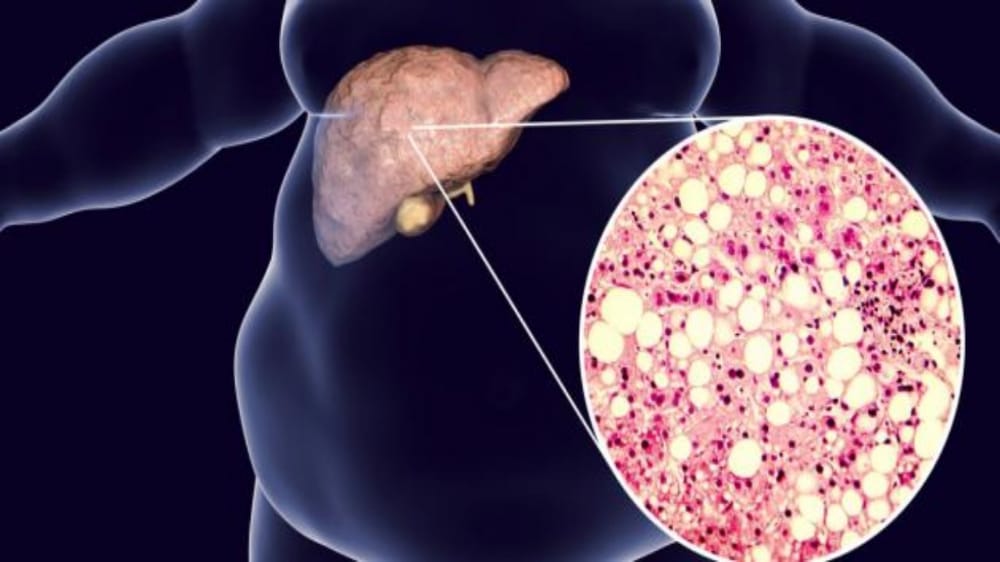

الخضيري: ترك الخبز والمخبوزات يقلل الدهون حول الكبد